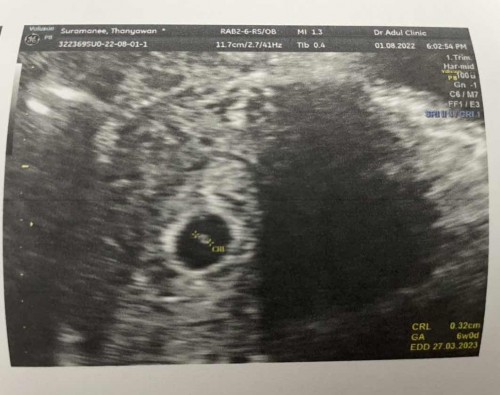

ของเราไปตรวจวันนี้ก็เจอเลย เพิ่ง6wเอง ดีใจมากเลยค่ะเห็นหัวใจดวงน้อยๆเต้นด้วย🥰